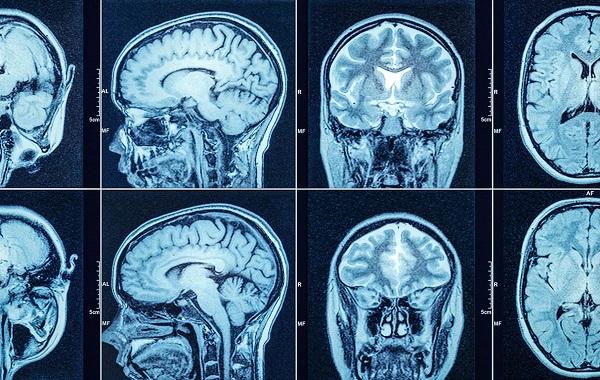

Chẩn đoán thiểu năng tuần hoàn não: Phát hiện sớm ngăn ngừa nguy hiểm

Thiểu năng tuần hoàn não xảy ra khi lượng máu và oxy đến não bị suy giảm, gây ra các triệu chứng như chóng mặt, đau đầu và suy giảm trí nhớ. Để xác định chính xác bạn có đang bị thiểu năng tuần hoàn não hay không cần phải...

Chẩn đoán thiếu máu não gồm những gì? Những lưu ý quan trọng khi thăm khám thiếu máu não

Để chẩn đoán thiếu máu não, bác sĩ chuyên khoa cần căn cứ trên các kết quả xét nghiệm, sau đó mới đưa ra phác đồ điều trị phù hợp nhất. Cụ thể chẩn đoán thiếu máu não gồm những gì? Khám phá ngay trong nội dung bài viết dưới...